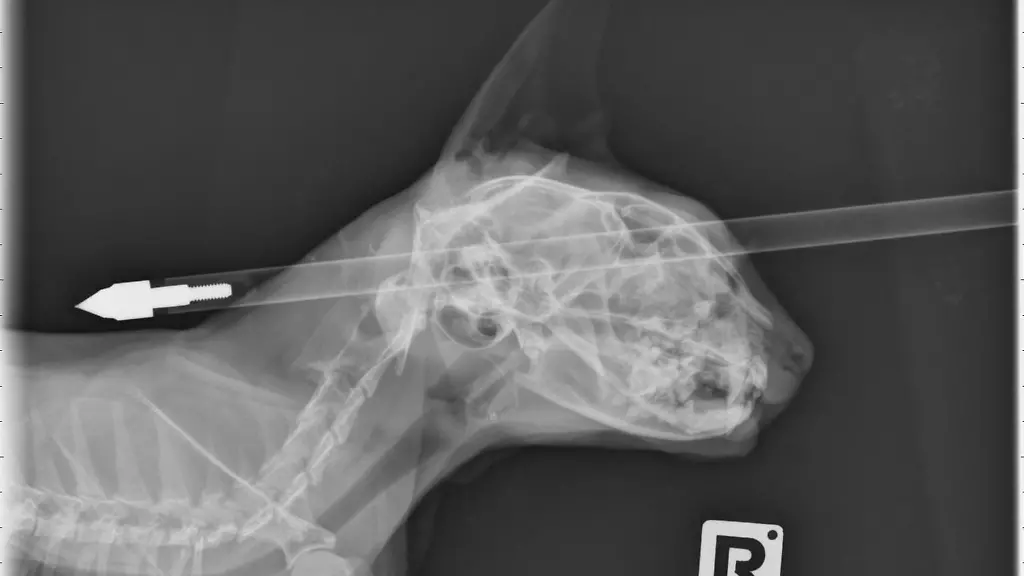

Der Pfeil durchschlug Kater Moo Moos Kopf, doch die Katze überlebte. Ein Unbekannter hatte mit einer Armbrust auf den vier Jahre alten Kater in Neuseeland geschossen. "Er hat sehr, sehr viel Glück gehabt", sagte Tierarzt Jonathan Bray. Tierärzte von der Massey-Universität hatten das Tier am Dienstag operiert. Der Pfeil hatte den Schädel des Katers völlig durchdrungen und ragte auf beiden Seiten aus dem Kopf des Tiers.

Allerdings hatte Moo Moo Glück im Unglück - der Pfeil traf die Katze oberhalb des Auges, streifte den Schädelknochen und verfehlte das Gehirn, erklärte Bray. "Die Gehirnmasse wurde nicht beschädigt." Das habe die Operation einfach gemacht. "Es gab eine kleine Verletzung an seiner Nase und seiner Augenhöhle."

Seine Besitzerin Donna Ferrari hatte den Kater gefunden und zunächst gedacht, es handle sich bei dem Pfeil um ein Kinderspielzeug. "Aber als er sich umdrehte, sah ich, das ging mitten durch seinen Kopf." Beinahe hätte sie ihm nicht helfen können, denn zunächst lief der Kater weg und es dauerte mehrere Stunden bis sie ihn mit Hilfe eine Nachbarn habe einfangen können. Der Tierarzt habe dann nicht schlecht gestaunt. So etwas habe er noch nie gesehen.